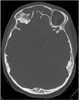

Frontal encephalocele

Encephalocele is a neural tube defect characterized by sac-like protrusions of the brain and the membranes that cover it through openings in the skull. These defects are caused by failure of the neural tube to close completely during fetal development. [Source: Wikipedia ]